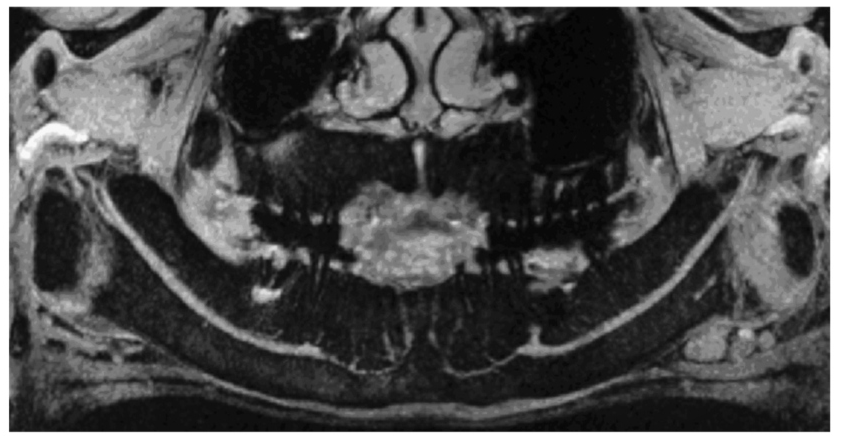

图4 MRI重建全景图像

显示的下牙槽神经管内神经走行分布,下牙槽神经行至回袢区分出细小分支继续前行,进入下颌切牙区

在全景片上可以见到神经管在第一、第二前磨牙之间向后上形成一个回袢样结构,开口于颏孔(图5)。